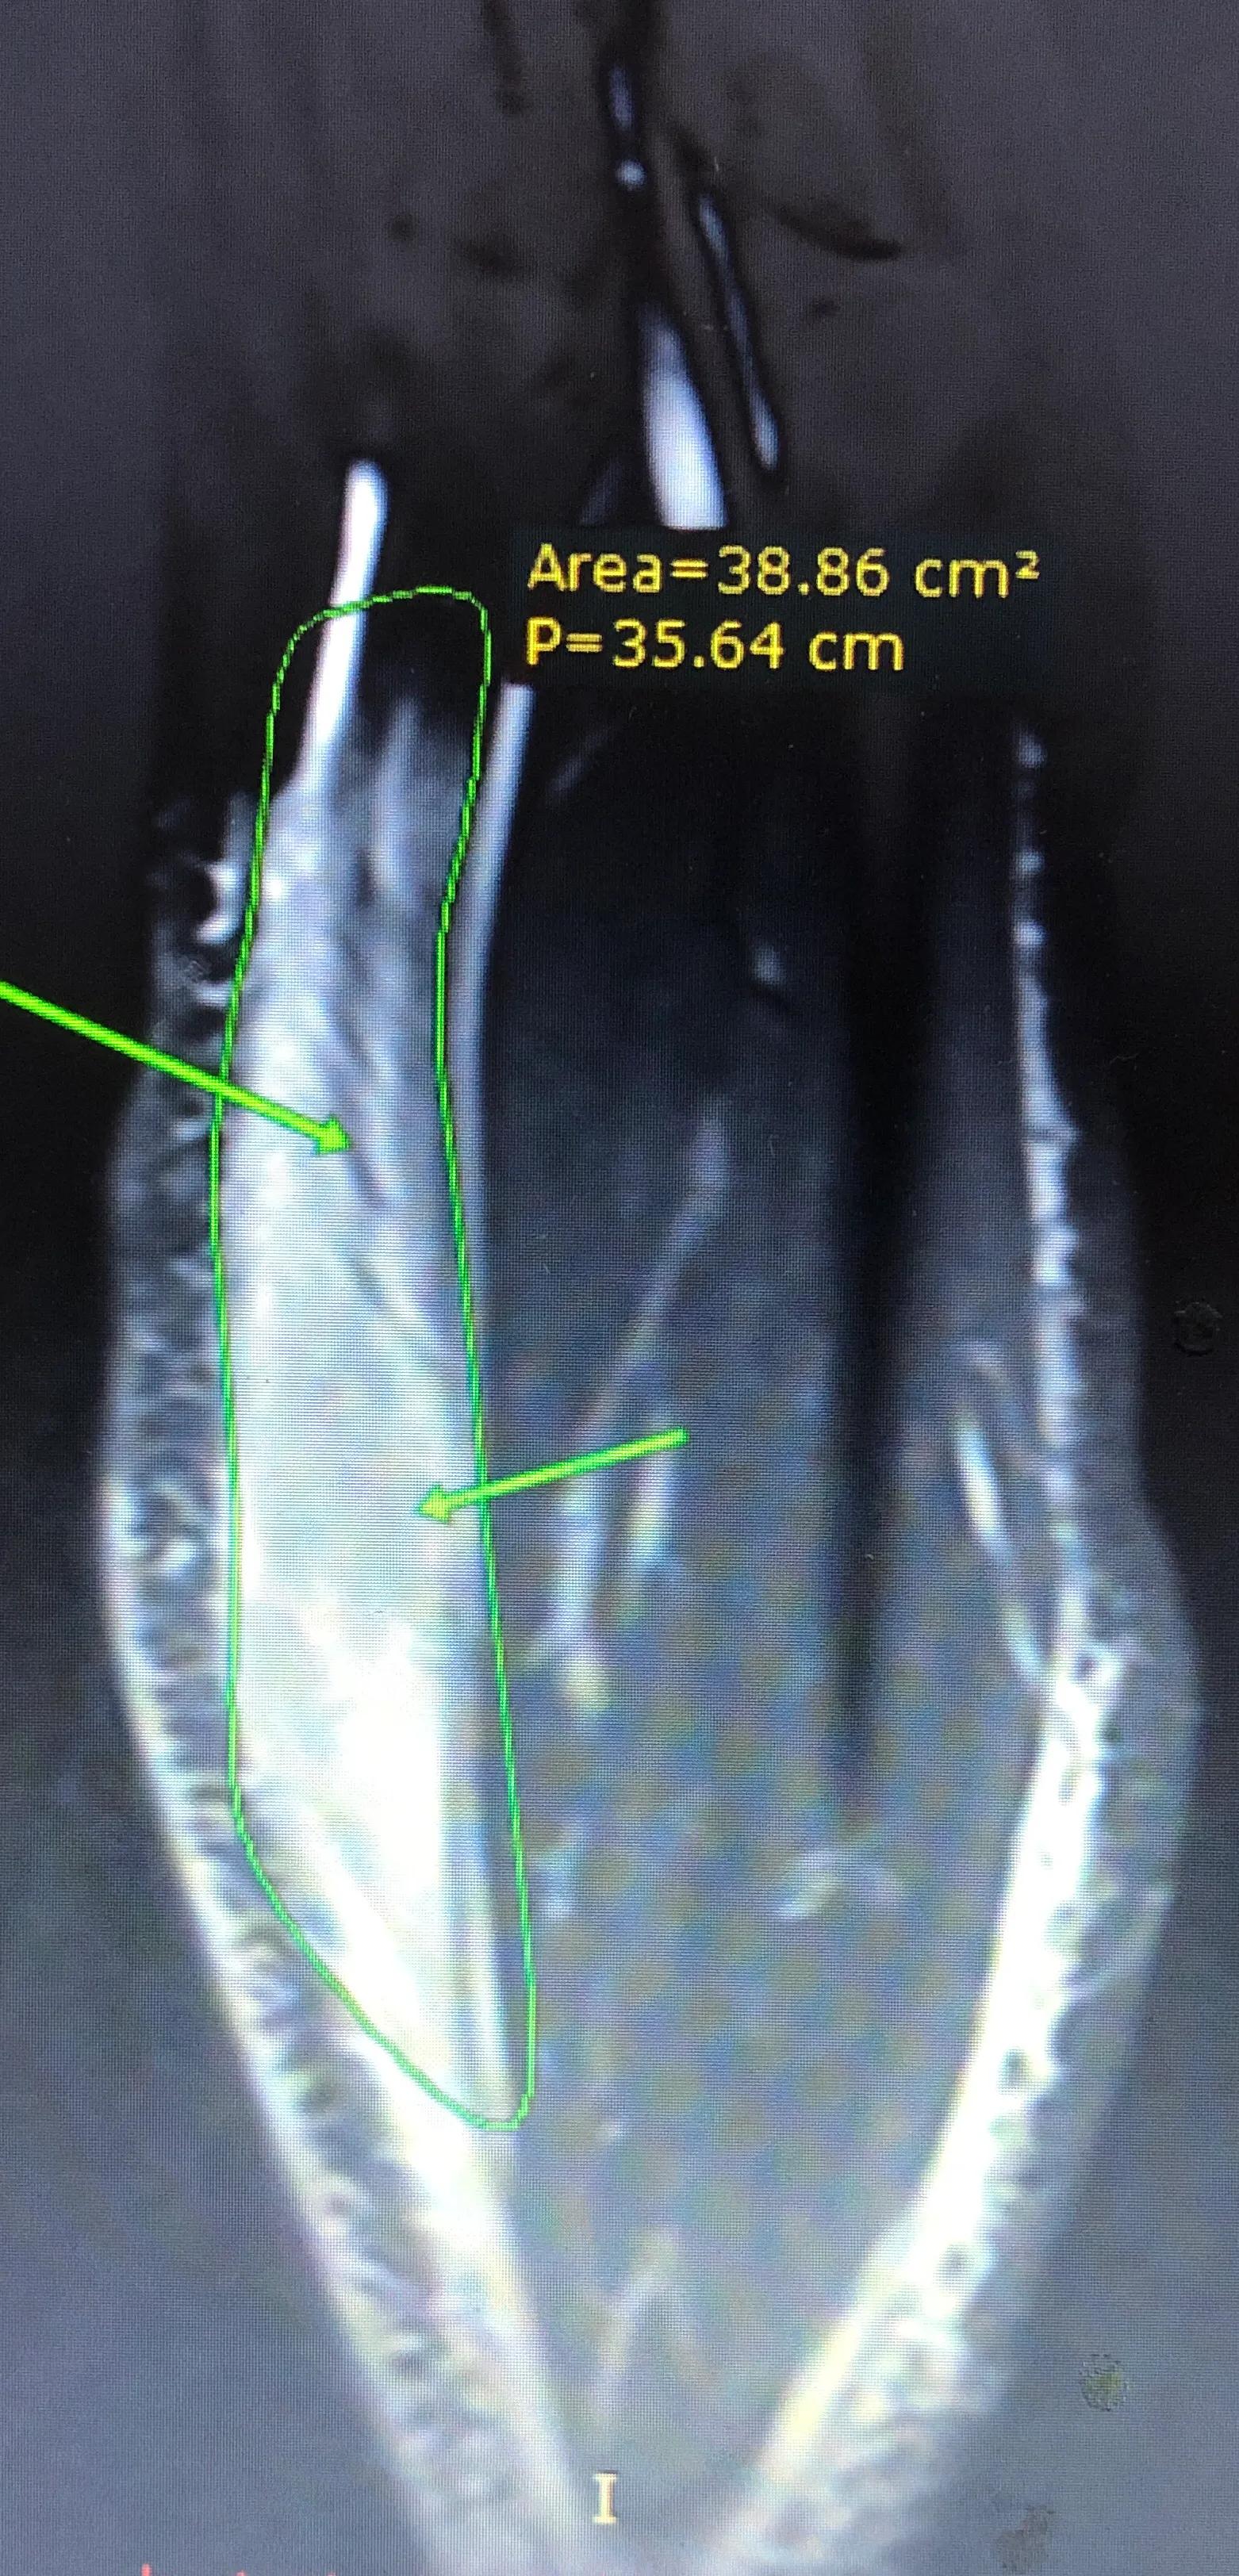

图4: 再一例大片撕裂的腓肠肌内侧头(绿色范围),与之相对的另外一块肌肉(腓肠肌外侧头)却正常,泾渭分明。